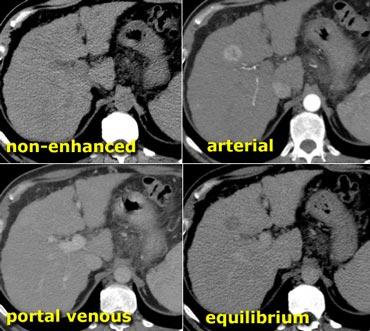

Hình bên trái minh họa tầm quan trọng của thì muộn ở bệnh nhân xơ gan có HCC.

Lưu ý rằng không thấy khối u trên hình chụp không tiêm thuốc và cũng không thấy trong thì tĩnh mạch cửa. Đây thường là trường hợp hay gặp và cho thấy tầm quan trọng của thì động mạch.

Vấn đề đặt ra là đối với các tổn thương ngấm thuốc nhỏ trên nền gan xơ, liệu đó là tổn thương lành tính như nốt tái tạo hay HCC.

Trong thì muộn, chúng ta thấy khối u thải thuốc nhiều hơn so với nhu mô gan xung quanh.

Các tổn thương lành tính thường không có kiểu thải thuốc này.

Ví dụ, FNH hoặc u tuyến sẽ ngấm thuốc nhanh trong thì động mạch, trở nên đồng tỷ trọng trong thì tĩnh mạch cửa, và vẫn đồng tỷ trọng với gan trong thì cân bằng.

Các khối u lành tính này không có đủ tân mạch tân sinh để thải thuốc nhanh.

Đặc biệt ở bệnh nhân xơ gan, cần dựa nhiều vào thì muộn này để phân biệt các tổn thương lành tính ngấm thuốc nhỏ với HCC kích thước nhỏ.

U máu gan trên CT không tiêm thuốc, thì động mạch muộn, thì tĩnh mạch cửa muộn và thì cân bằng. Lưu ý tỷ trọng của u máu tương đương với hồ máu trong tất cả các thì (mũi tên).

Hồ máu và U máu gan

Thông thường khi đánh giá các tổn thương ngấm thuốc, tỷ trọng của tổn thương luôn được so sánh với tỷ trọng của nhu mô gan.

Tuy nhiên, đối với u máu gan, không nên so sánh tỷ trọng của tổn thương với gan mà phải so sánh với hồ máu.

Điều này có nghĩa là các vùng ngấm thuốc trong u máu phải tương đương với tỷ trọng của các mạch máu tương ứng (hồ máu) ở mọi thời điểm.

Vì vậy, trong thì động mạch, các phần ngấm thuốc của tổn thương phải có giá trị tỷ trọng gần bằng với động mạch chủ đang ngấm thuốc, trong khi ở thì tĩnh mạch cửa phải tương đương với sự ngấm thuốc của tĩnh mạch cửa.

Nếu tỷ trọng không tương đương với hồ máu trong tất cả các thì tiêm thuốc, hãy loại bỏ chẩn đoán u máu gan.

Hình bên trái là một u máu gan điển hình.

Lưu ý rằng trên CT không tiêm thuốc, tỷ trọng của khối u tương đương với tỷ trọng của các mạch máu.

Trong thì động mạch, tỷ trọng tương đương với hồ máu và gần bằng với động mạch chủ.

Trong thì tĩnh mạch cửa, tỷ trọng tương đương với tĩnh mạch cửa.

Trong thì cân bằng, tỷ trọng ngấm thuốc tương đương với các mạch máu.

Cuối cùng tổn thương sẽ trở nên đồng tỷ trọng với gan, nhưng chỉ vì các mạch máu cũng trở nên đồng tỷ trọng với gan.

Điều này không liên quan đến tỷ trọng của bản thân nhu mô gan.

Vì vậy, hãy nghĩ đến hồ máu thay vì gan khi nghĩ đến u máu gan.